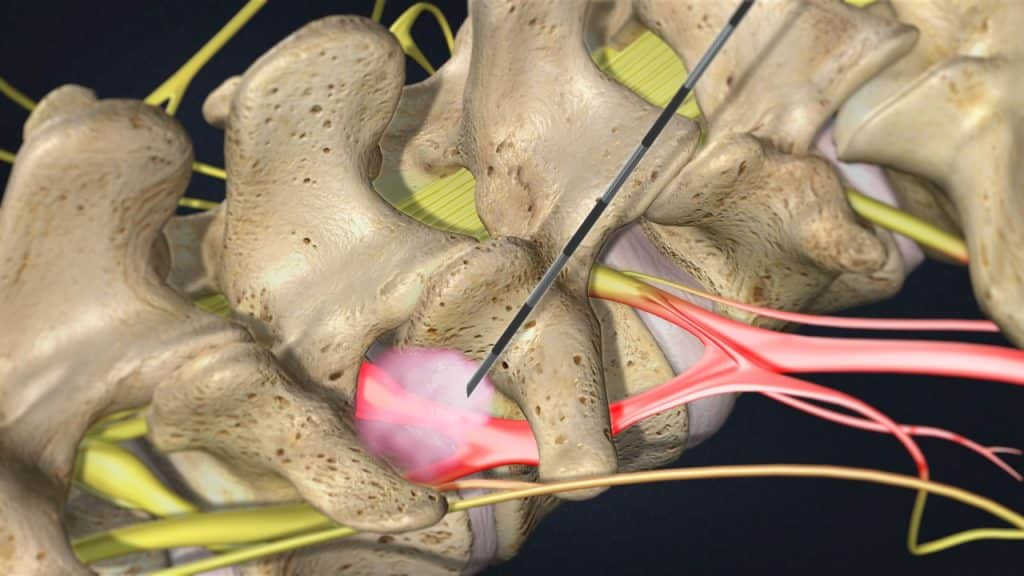

Эти заболевания можно лечить с помощью обезболивания и десенсибилизации раздраженного нервного корешка. Для этого, вводятся местный анестетик и кортикостероиды в переднее эпидуральное пространство через межпозвонковые отверстия, то есть в точки выхода нервного корешка из позвоночника. Этот метод применяется под радиоскопическим контролем.